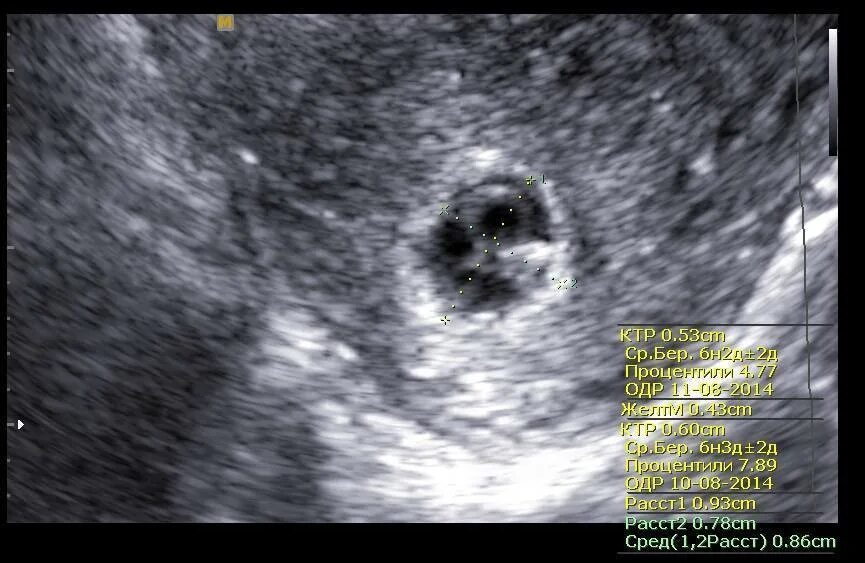

Плодном яйце не визуализируется эмбрион